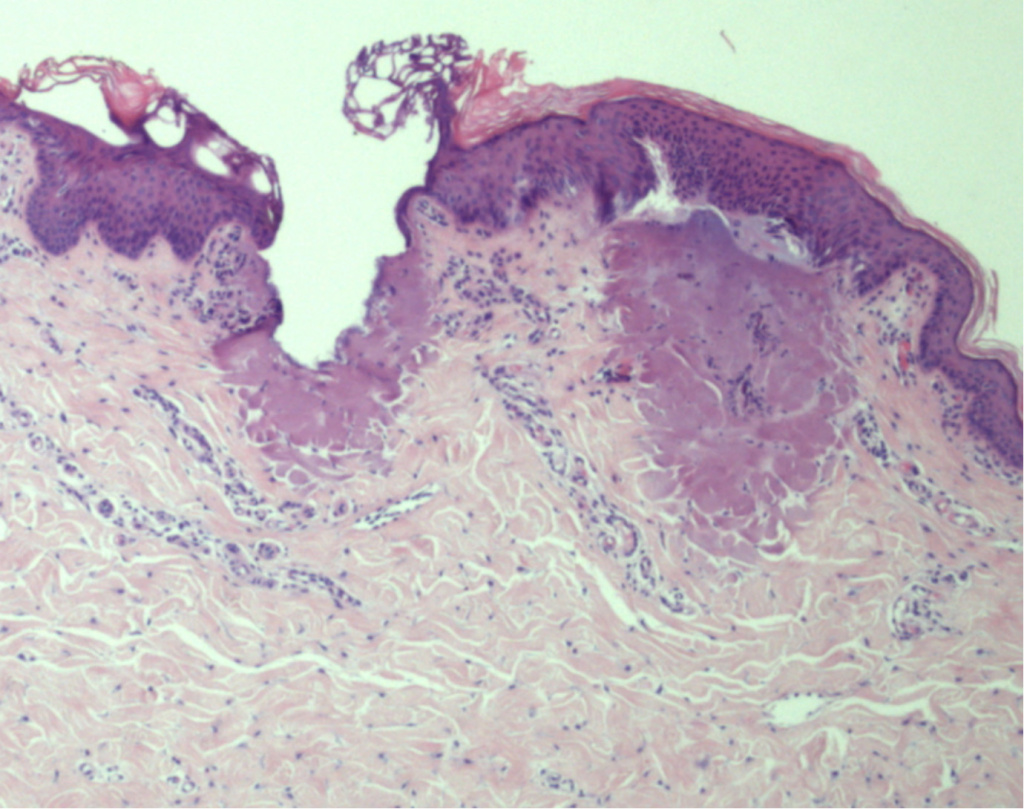

Гистологическое сравнение воздействия CO₂, 1570 нм и HyGrid